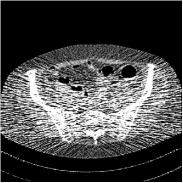

Refer to caption FBPRMSE = 194.09 HURefer to caption FBPRMSE = 194.09 HURefer to caption PWLS-ULTRARMSE = 43.40 HURefer to caption PWLS-ULTRARMSE = 43.40 HU

Refer to caption FBPConvNetRMSE = 34.24 HURefer to caption FBPConvNetRMSE = 34.24 HURefer to caption SUPER-FCN-DataTermRMSE = 31.21 HURefer to caption SUPER-FCN-DataTermRMSE = 31.21 HU

Refer to caption SUPER-FCN-ULTRARMSE = 28.82 HURefer to caption SUPER-FCN-ULTRARMSE = 28.82 HURefer to caption ReferenceRefer to caption Reference

Figure 5: Reconstructed images of slice 150 of patient L192 using of FBP, PWLS-ULTRA, FBPConvNet, SUPER-FCN-DataTerm, and SUPER-FCN-ULTRA, respectively, shown along with the reference.

Fig. 5 shows reconstructions using FBPConvNet, SUPER-FCN-DataTerm (i.e., β=μ=0𝛽𝜇0\beta=\mu=0), PWLS-ULTRA, and SUPER-FCN-ULTRA, respectively. For SUPER-FCN-DataTerm, when optimizing the data-fidelity term, we start with the deep network’s output and ran 5 iterations for the data-fidelity term to avoid overfitting to the analytical FBP images. In Fig. 5, obviously, FBPConvNet significantly suppresses noise and artifacts compared to PWLS-ULTRA, but it also over-smooths many details (e.g., features in the zoom-in box) in the reconstruction. SUPER-FCN-DataTerm, by enforcing data consistency, helps reduce overfitting issues and reconstructs image details and tissue boundaries better compared to the standalone FBPConvNet. Our SUPER-FCN-ULTRA method, however, exploits richer prior information (via the union of learned sparsifying transforms) and explicit network regularizer and outperforms the SUPER-FCN-DataTerm approach. Additional such comparisons for other selected test slices are included in the supplement (Fig. 15).